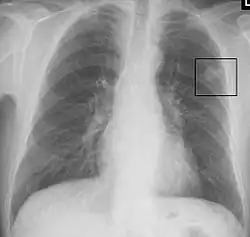

Le cancer du poumon peut être vu sur les radiographies thoraciques et le scanner. Le diagnostic est confirmé par une biopsie. Ceci se fait généralement par bronchoscopie, ou par biopsie guidée par scanner. Le traitement et le pronostic dépendent du type histologique du cancer, de son stade (degré de dissémination), et de l'état général de santé du patient.

Beaucoup des symptômes du cancer du poumon (douleurs osseuses, fièvre et perte de poids) sont non spécifiques ; chez les patients âgés, ils peuvent être attribués à une comorbidité[4]. Chez beaucoup de patients, le cancer s'est déjà étendu au-delà du site original au moment où le patient ressent les premiers symptômes et consulte. Des sites fréquents de métastases sont le cerveau, les os, les glandes surrénales, le poumon controlatéral (de l'autre côté), le foie, le péricarde et les reins[133]. Environ 10 % de tous les patients atteints par le cancer du poumon n'ont pas de symptôme diagnostic ; ces cancers sont découverts par hasard à la suite d'une radiographie de la poitrine[3].

La radiographie thoracique est la première mesure à prendre si un patient se plaint de symptômes pouvant suggérer un cancer du poumon. Ceci peut révéler une masse évidente, un élargissement du médiastin (qui suggère une extension aux ganglions lymphatiques qui s'y trouvent), une atélectasie (affaissement), une inflammation (pneumonie) ou un épanchement pleural. En l'absence de signes radiographiques, mais si les soupçons sont élevés (par exemple, un gros fumeur avec hémoptysie), une bronchoscopie ou un scanner peuvent donner l'information nécessaire. La bronchoscopie ou la biopsie guidée par scanner sont souvent utilisées pour identifier le type de tumeur[3].

Le diagnostic différentiel pour les patients qui présentent des anomalies de la radiographie thoracique consiste à distinguer le cancer du poumon des maladies non malignes. Ces dernières peuvent être des infections, telles que la tuberculose ou la pneumonie, ou des inflammations comme la sarcoïdose. Ces maladies peuvent donner lieu à des lymphadénopathies du médiastin, ou à des nodules du poumon, qui peuvent imiter des cancers du poumon[4]. Le cancer du poumon peut par contre être une trouvaille incidentelle : un nodule pulmonaire solitaire (lésion en « pièce de monnaie ») vu sur une radiographie du thorax ou un scanner pris pour une tout autre raison.